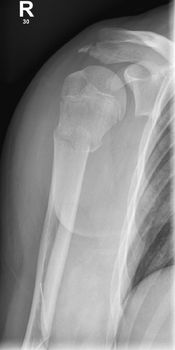

Abb 1: Dislozierter suprakondylärer Humerusfraktur behandelt mit K-Draht Osteosynthese

Abb 2: Subkapitale Humerusfraktur, Z.n. geschlossene Reposition sowie Stabilisierung mit TENS